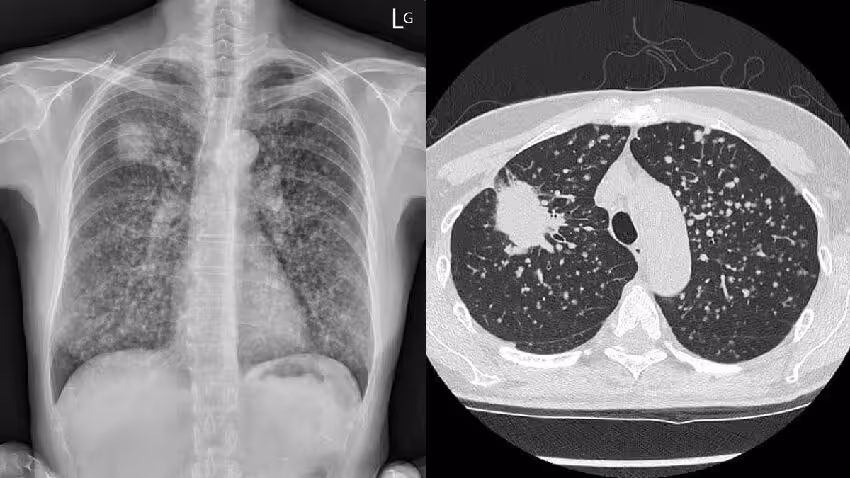

許多醫護朋友看個案年輕又咳嗽1個月,馬上懷疑是否有抽煙:「這個GGO (毛玻璃樣病灶,Ground Glass Opacity) 好像沒有很明顯?

煙抽很久嗎」、「請問他有抽煙嗎」,蘇醫師指出男病患雖年輕,但煙齡已經有2、30年了。